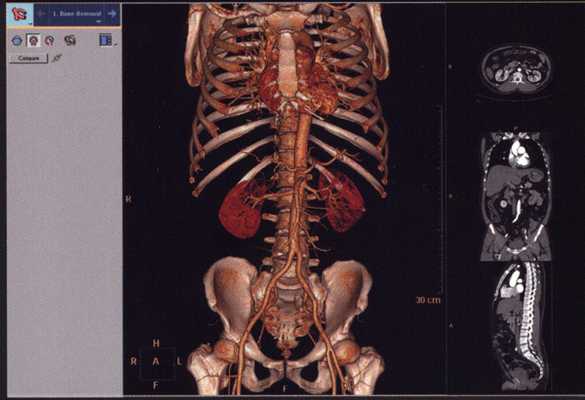

Для уточнения локализации и размеров патологического очага врач может использовать пространственное изображение области интереса . На основании фотографий, полученных в результате сканирования, реконструируют 3D-модель рассматриваемой зоны. Трехмерная визуализация позволяет оценить характер взаимодействия здоровых и пораженных тканей.

КТ внутренних органов что показывает

Компьютерная томография - высокоинформативное исследование, позволяющее обнаружить патологические изменения внутри организма без инвазивного проникновения: диагностические манипуляции не нарушают целостность тканей, как при лапароскопии. Множество срезов в поперечной проекции обрабатывает специальная программа. При помощи реконструкции получают изображения в других плоскостях и объемную модель зоны интереса.

На снимках видны нормальные анатомические структуры и отклонения